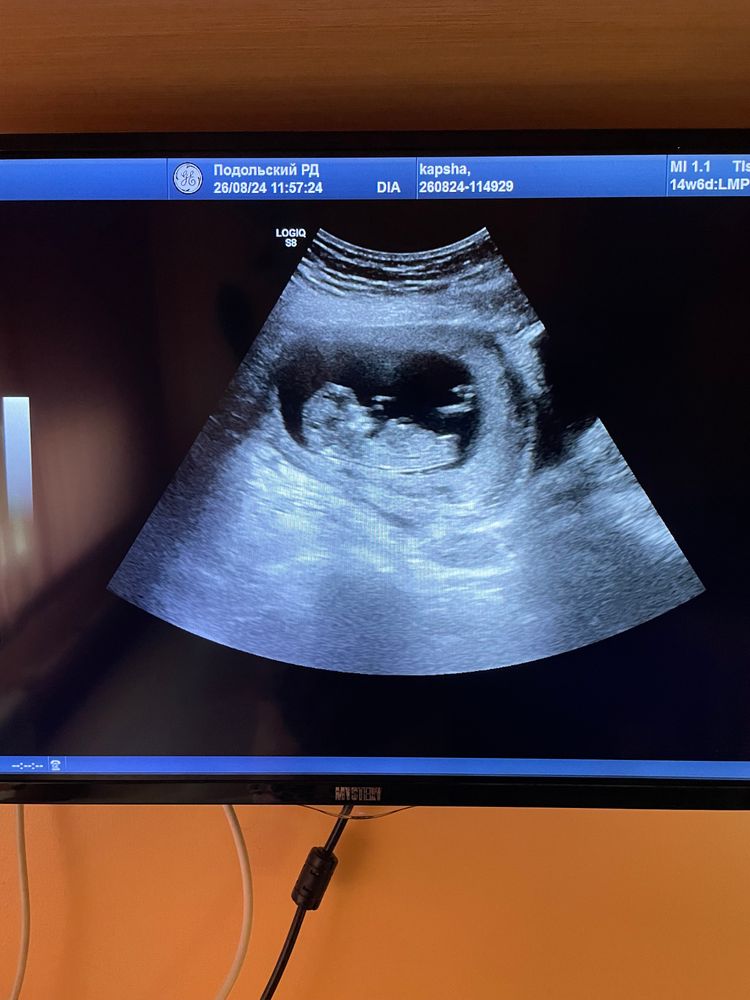

Юлия , вот наше узи в 12 недель) предполагали девочку, так и оказалось в итоге) Изображение

31.01.2025